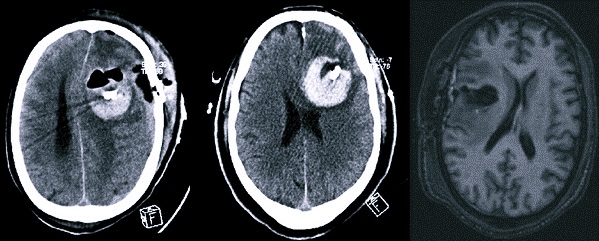

Компьютерная томография

Компьютерная томография – менее информативный метод. С помощью КТ можно определить точное место локализации новообразования, а также сопутствующие симптомы, например, гематому и отечность.

Компьютерная томография – одно из основных исследований, необходимых для выявления мозговой опухоли

Магнитно-резонансная томография

Магнитно-резонансная томография – наиболее достоверный метод выявления мозговых опухолей. Вид новообразования на снимке представлен в форме трехмерного изображения и в тончайшем разрезе. На начальном этапе развития болезни образование на снимке выглядит в форме отека.

Диагностическому мероприятию под силу выявить даже мелкое новообразование, а также образование, место которого – возле кости или мозгового ствола.